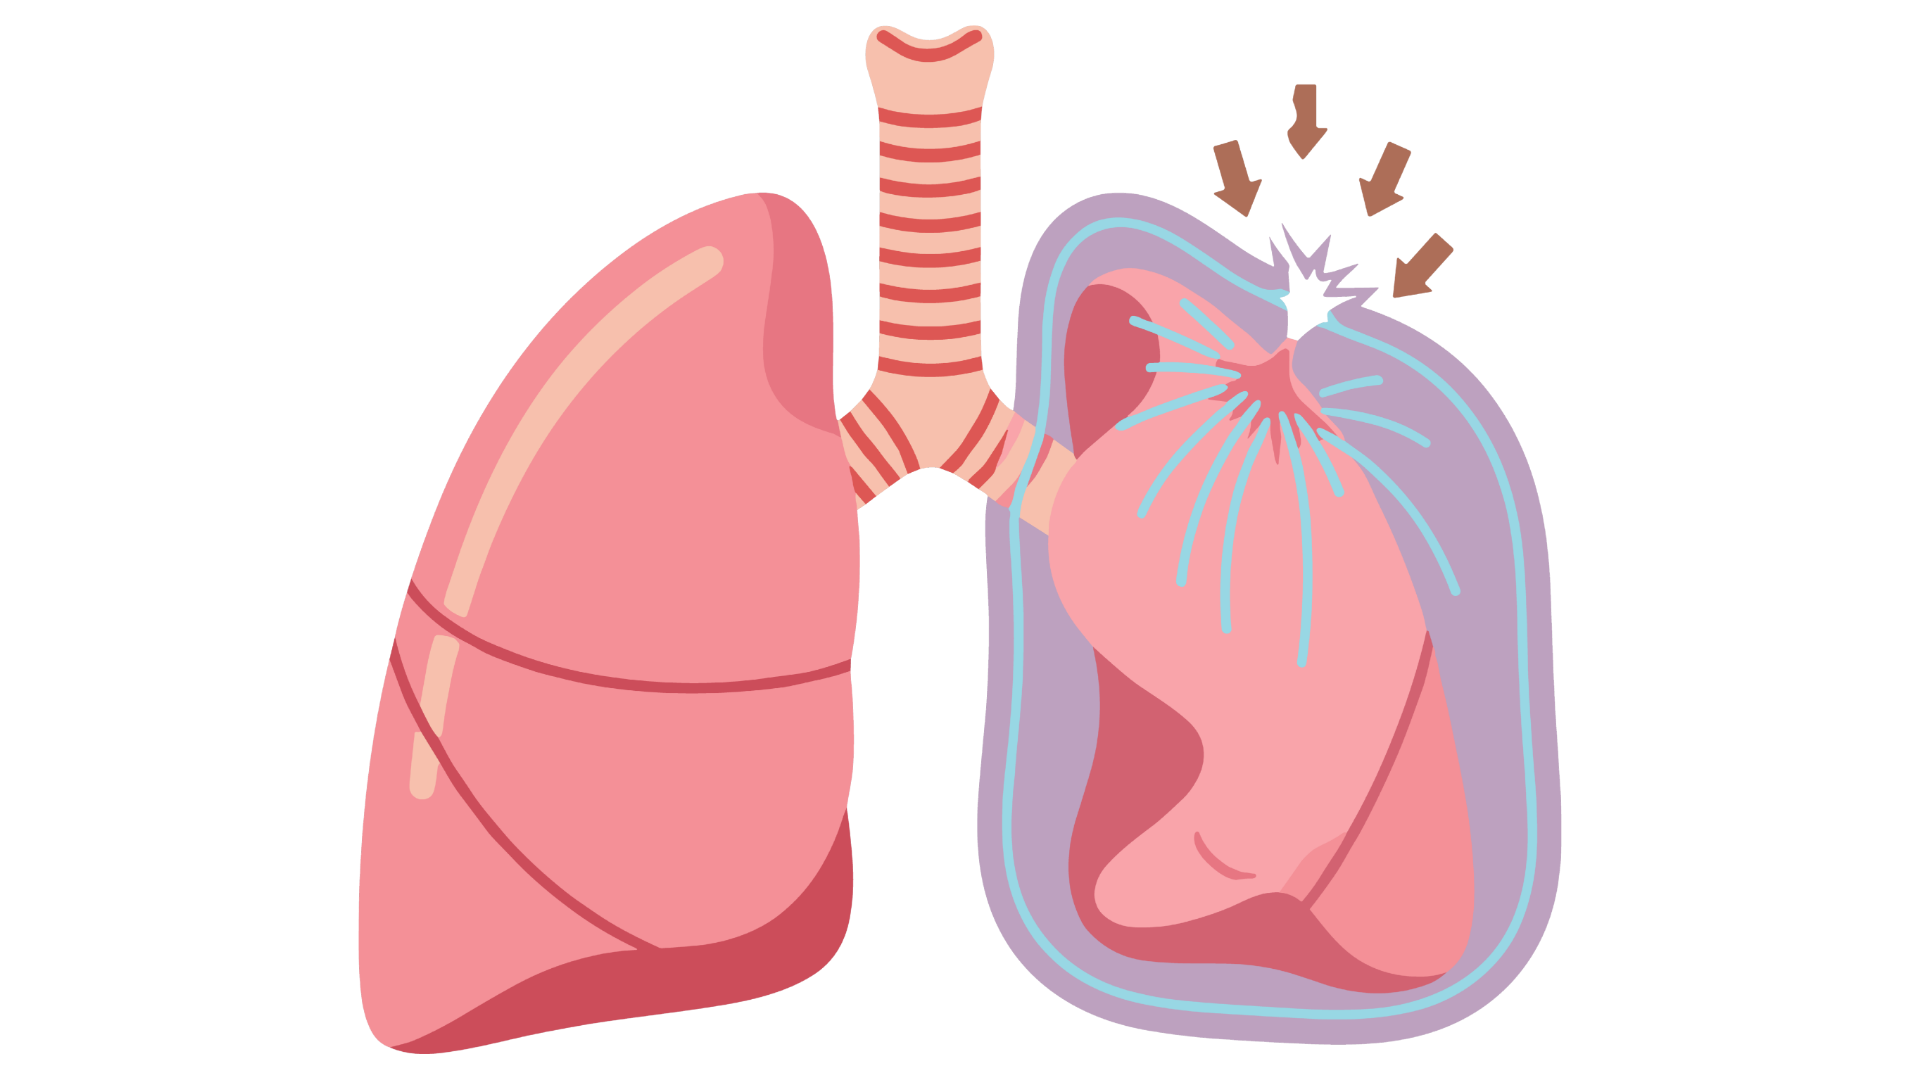

- rozpoznania i postępowania w odmie prężnej

- odbarczenia igłowego odmy prężnej

- wykonanie finger thoracostomy